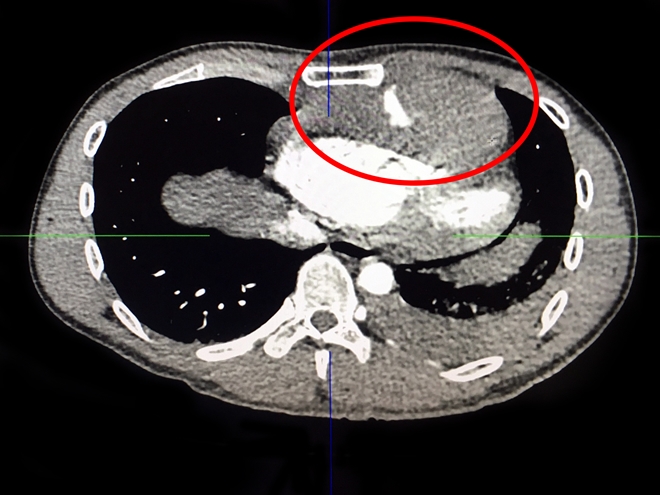

Thông tin tối ngày 3-4 từ Bệnh viện Xuyên Á (BVXA) cho hay, các bác sĩ vừa cứu sống bệnh nhân N.L.A.T. (32 tuổi, ngụ tại huyện Đức Hòa, tỉnh Long An). Trước đó, anh T. dùng dao Thái Lan tự đâm vào ngực mình để tự tử, vết thương thấu ngực sát tim, đứt động mạch cực kì nguy hiểm.